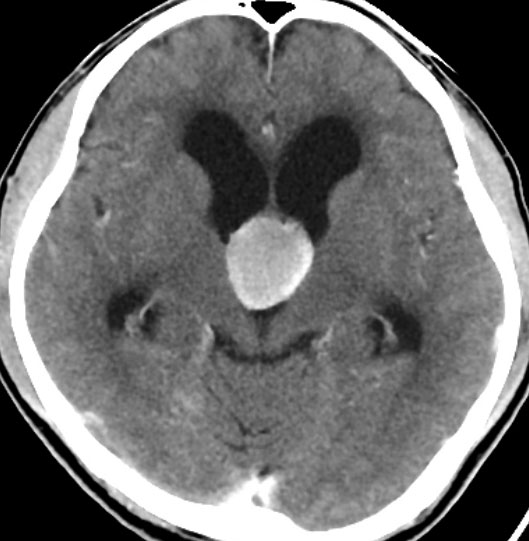

第3脳室内にはさまざまな嚢胞性病変が発生しますが,第3脳室内部の発生母地で鑑別ができます。例えば,前上方に類円形の腫瘤を認めたときにはコロイドのう胞をもっとも強く疑い,逆に後方であればのう胞性松果体腫瘍を疑います。一般的にCTでは等吸収から高吸収域を示し,MRIではT1, T2強調画像ともに高信号を呈することが多いといえます。造影剤で嚢胞壁の増強効果を認めることはとても稀です。

CTでは壁が厚く高密度,MRI T2強調画像では低信号,T1強調画像では高信号です。内部に血液を含んでいるようなのう胞に見えます。のう胞の壁は非常に厚く硬いものが予想されます。閉塞性水頭症になっています。